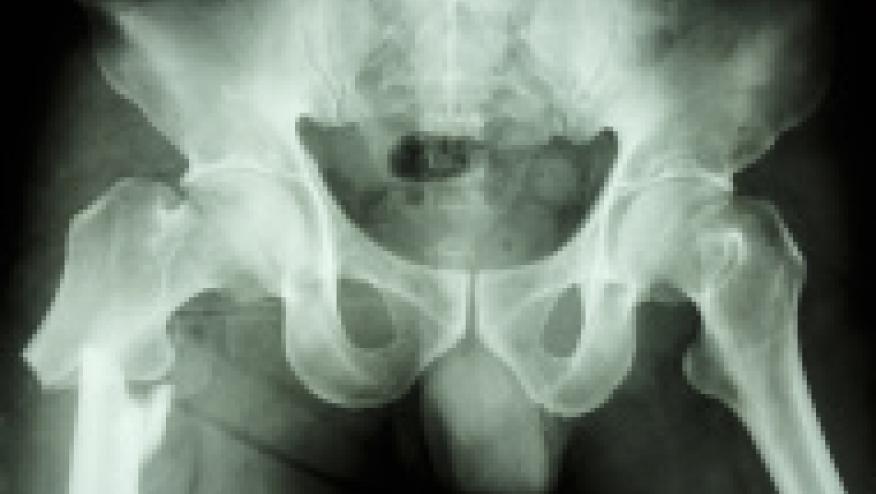

People who are older than 80 should be considered for osteoporosis treatment after a fracture to avoid further risk, according to a study being presented Saturday at ENDO 2025, the Endocrine Society’s annual meeting in San Francisco, Calif.

“The burden of osteoporosis is rising as the global population ages rapidly,” said Gianina Flocco, M.D., a resident at the Cleveland Clinic in Cleveland, Ohio. “Our study supports the initiation of osteoporosis treatment after a fracture in people older than 80 years, as it has been shown to decrease both hospitalization and mortality.”

Flocco and colleagues used the TriNextX health research database to study 88,676 patients aged 80 and older who suffered a fracture due to bone deterioration or weakness caused by osteoporosis.